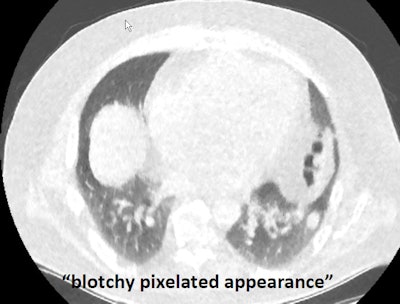

But no matter how good the reconstruction scheme, ultralow-dose imaging acquisition might be challenged in areas such as near the shoulders, where thicker, denser tissues could potentially create more localized noise and obscure visualization of the lungs, she said. Readers have also noted the blotchy, pixelated appearance of MBIR scans that might make them difficult to read.

"Despite this blotchy, plastic-y, different sort of look to the lung tissue, we can still see quite small pulmonary nodules ... it's just not the pretty picture of yesteryear," she said.

Ultralow-dose CT image of the lungs reconstructed with MBIR looks blotchy and pixelated, but small nodules can still be found.It's not all about noise and detection; CT must perform a number of functions to be acceptable for lung scans, Kazerooni said. It must detect and characterize nodules and be able to follow them serially over time. Radiologists categorize nodules as solid, part-solid, or ground glass, and CT must permit nodules to be quantified using 2D or 3D techniques.